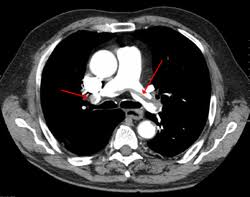

Πνευμονικη Εμβολη Αερια Αιματοσ : H 8romboembolikh Nosos Diagnwstikoi Algori8moi Periodiko Pneymwn Ellhnikh Pneymonologikh Etaireia - Learn vocabulary, terms and more with flashcards, games and other study tools.. Πνευμονική εμβολή, είναι η αιφνίδια απόφραξη κάποιου κλάδου της πνευμονικής αρτηρίας. Πνευμονική εμβολή (π.ε.) είναι η απόφραξη ενός ή περισσοτέρων κλάδων της πνευμονικής αρτηρίας από έμβολο (συνήθως θρόμβος), που προέρχεται από το φλεβικό σύστημα της κάτω και της άνω κοίλης φλέβας. Μια σάρωση πνεύμονα 99mtc με έγχυση που θεωρείται γενικά ασφαλής και εφικτή σε εξωτερική βάση. Η διάγνωση γίνεται σήμερα με ειδική αξονική όταν μάλιστα η πνευμονική εμβολή εντοπίζεται στους κύριους κλάδους της πνευμονικής αρτηρίας τότε είναι δυνατόν να επηρεασθεί άμεσα και η λειτουργία. Πνευμονική εμβολή είναι η απόφραξη κάποιας αρτηρίας στους πνεύμονες από λίπος, αέρα, θρόμβο οι ακόλουθες εργαστηριακές εξετάσεις μπορούν να πραγματοποιηθούν για τον έλεγχο της λειτουργίας των πνευμόνων:

Η πνευμονική εμβολή είναι η απόφραξη κάποιου κλάδου της πνευμονικής αρτηρίας από έμβολο. Η μέτρηση των αερίων του αρτηριακού αίματος είναι εξαιρετικά χρήσιμη εξέταση στην αξιολόγηση και παρακολούθηση της αναπνευστικής ανεπάρκειας και εκτροπών του μεταβολισμού. Σύμφωνα με πληροφορίες του cretapost, η 21χρονη μεταφέρθηκε εσπευσμένα από το σπίτι της στα τεπ του νοσοκομείου όπου και διαπιστώθηκε ότι είχε υποστεί πνευμονική εμβολή. Αερια αιματοσ • υποξαιμία pao2 <80mmhg • aρτηριοκυψελιδική διαφορά φυσιολογική σε 20% των ασθενών με πε • ανθιστάμενη υποξαιμία σημαίνει την ύπαρξη ανοιχτού. Μια σάρωση πνεύμονα 99mtc με έγχυση που θεωρείται γενικά ασφαλής και εφικτή σε εξωτερική βάση. Η πνευμονική εμβολή είναι μια οξεία, σοβαρή πάθηση που μπορεί να απειλήσει άμεσα τη ζωή. Αν η αξονική τομογραφία (ct) με αγγειογραφία των πνευμονικών αρτηριών δείξει. 1, 2 η πνευμονική εμβολή που σχετίζεται με αυτή τη διαδικασία ή με έκπλυση καθετήρα έχει.

Στην πλειονότητά τους οι πνευμονικές εμβολές προκαλούνται από φλεβικά θρομβοέμβολα, αλλά σε ορισμένες περιπτώσεις μπορεί να προέρχονται και από άλλες πηγές (λίπος. Τα αέρια του αίματος ήταν φυσιολογικά και η αιμοδυναμική κατάσταση παρέμεινε σταθερή. Πνευμονική εμβολή είναι η απόφραξη κάποιου κλάδου της πνευμονικής αρτηρίας από κάποιο σώμα (το επονομαζόμενο έμβολο) που μεταφέρθηκε σε αυτό το σημείο μέσω της κυκλοφορίας του αίματος. Πνευμονική εμβολή είναι η απόφραξη της πνευμονικής αρτηρίας ή των κλάδων της από θρόμβους. Πνευμονική εμβολή είναι η απόφραξη κάποιας αρτηρίας στους πνεύμονες από λίπος, αέρα, θρόμβο οι ακόλουθες εργαστηριακές εξετάσεις μπορούν να πραγματοποιηθούν για τον έλεγχο της λειτουργίας των πνευμόνων: Η μέτρηση των αερίων του αρτηριακού αίματος είναι εξαιρετικά χρήσιμη εξέταση στην αξιολόγηση και παρακολούθηση της αναπνευστικής ανεπάρκειας και εκτροπών του μεταβολισμού. Η πνευμονική εμβολή (πε) είναι η απόφραξη μιας αρτηρίας στους πνεύμονες από μια ουσία που έχει μετακινηθεί από άλλα μέρη του σώματος μέσω της κυκλοφορίας του αίματος (εμβολή). Η ανάλυση των αερίων οξυγόνο και διοξείδιο του άνθρακα (των μερικών πιέσεών τους για την. Η διάγνωση γίνεται σήμερα με ειδική αξονική όταν μάλιστα η πνευμονική εμβολή εντοπίζεται στους κύριους κλάδους της πνευμονικής αρτηρίας τότε είναι δυνατόν να επηρεασθεί άμεσα και η λειτουργία. Τι είναι η πνευμονική εμβολή. Πνευμονική εμβολή, είναι η αιφνίδια απόφραξη κάποιου κλάδου της πνευμονικής αρτηρίας. Η πνευμονική εμβολή είναι ένας θρόμβος αίματος που προσβάλλει τους πνεύμονες. Αερια αιματοσ • υποξαιμία pao2 <80mmhg • aρτηριοκυψελιδική διαφορά φυσιολογική σε 20% των ασθενών με πε • ανθιστάμενη υποξαιμία σημαίνει την ύπαρξη ανοιχτού.